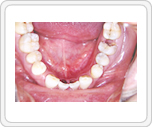

■治療前

左下第1大臼歯の虫歯は神経まで達していました。全体に虫歯が多く存在し、このままでは咬合崩壊の危険性がある状態でした。